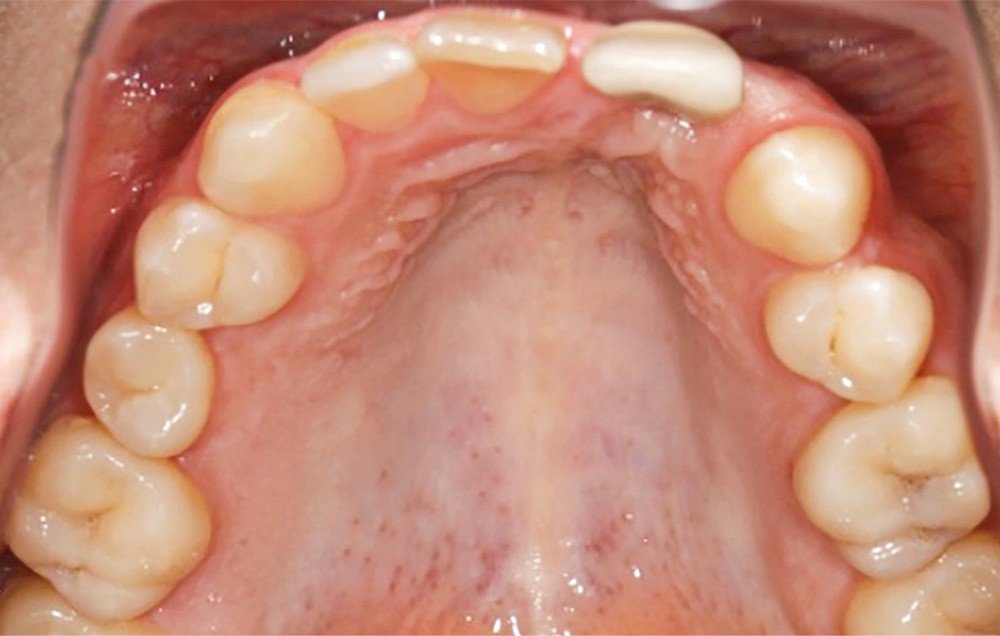

- au niveau esthétique : une couronne sur 21 disgracieuse et une déviation du milieu maxillaire vers la gauche (fig. 2) ;

- au niveau dentaire : une arcade maxillaire asymétrique avec déviation du milieu maxillaire à gauche. On note l’absence de 21, 22, 25, 35 et 45, une classe II droite et gauche avec infraclusion antérieure et la présence d’un implant en place de 21 avec un diastème de 3 mm entre 21 et 23 (fig. 3) ;